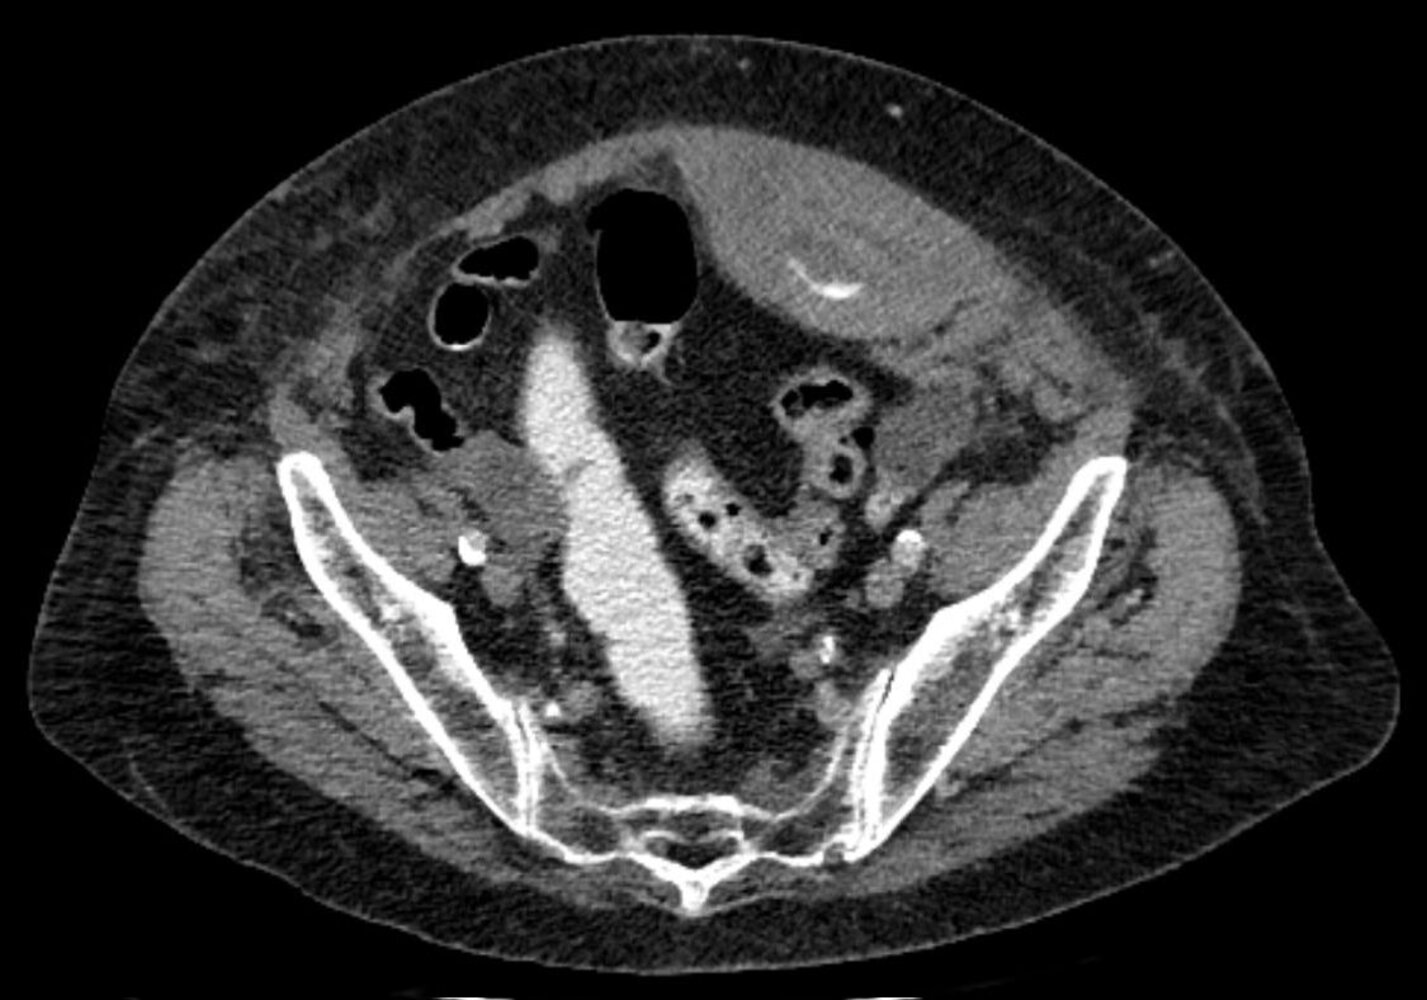

• CT abdomen

• Sensitive imaging study for suspected bowel obstruction or strangulation [10]

• Typically performed with both IV and PO contrast (unless contraindicated because of obstruction)

• Can facilitate planning for complex hernia repair [23]

Findings

• Direct visualization and quantification of the fascial defect(s)

• Presence of viscera in the hernial sac

• Strangulated hernia: signs of visceral ischemia [25]

• Obstructed hernia: radiological signs of mechanical bowel obstruction